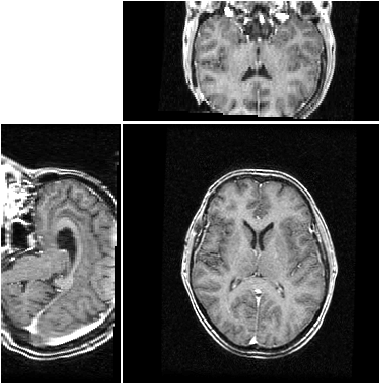

Dans le cadre du projet AGIR, l'équipe Rainbow s'intéresse à la comparaison d'algorithme de recalage d'images 3D. Le recalage d'images consiste à aligner différentes images pour les faires coincider au mieux:

| ![]() | |

| sans recalage | avec recalage |

Ces algorithmes sont coûteux en calculs et l'utilisation de grille de calcul a permis de tester plusieurs algorithmes existants sur des grandes bases de données. Cependant, seule des méthodes utilisant des transformations globales des images ont été utilisées. Ces transformations correspondent pas exemple au fait qu'un patient a pu bouger la tête au cours d'une acquisition IRM. Lorsque l'on veut comparer des images prises à des époques différentes ou bien comparer des images issus de plusieurs patients, ces transformations globales ne suffisent plus: il faut également tenir compte de transformations locales: